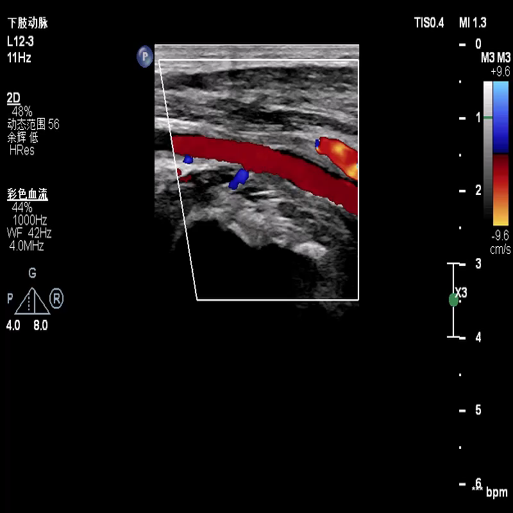

图:a) 穿刺后导丝置入;

图:b) 吸栓装置定位;

图:c) 球囊扩张股浅动脉时球囊远心端显像;

图:d)球囊扩张股浅动脉开口处显像,同时附带血流显像;

图:e)术前评估时腘动脉未见血流图像;

图:f)经吸栓、球囊扩张等治疗措施后腘动脉血流图像